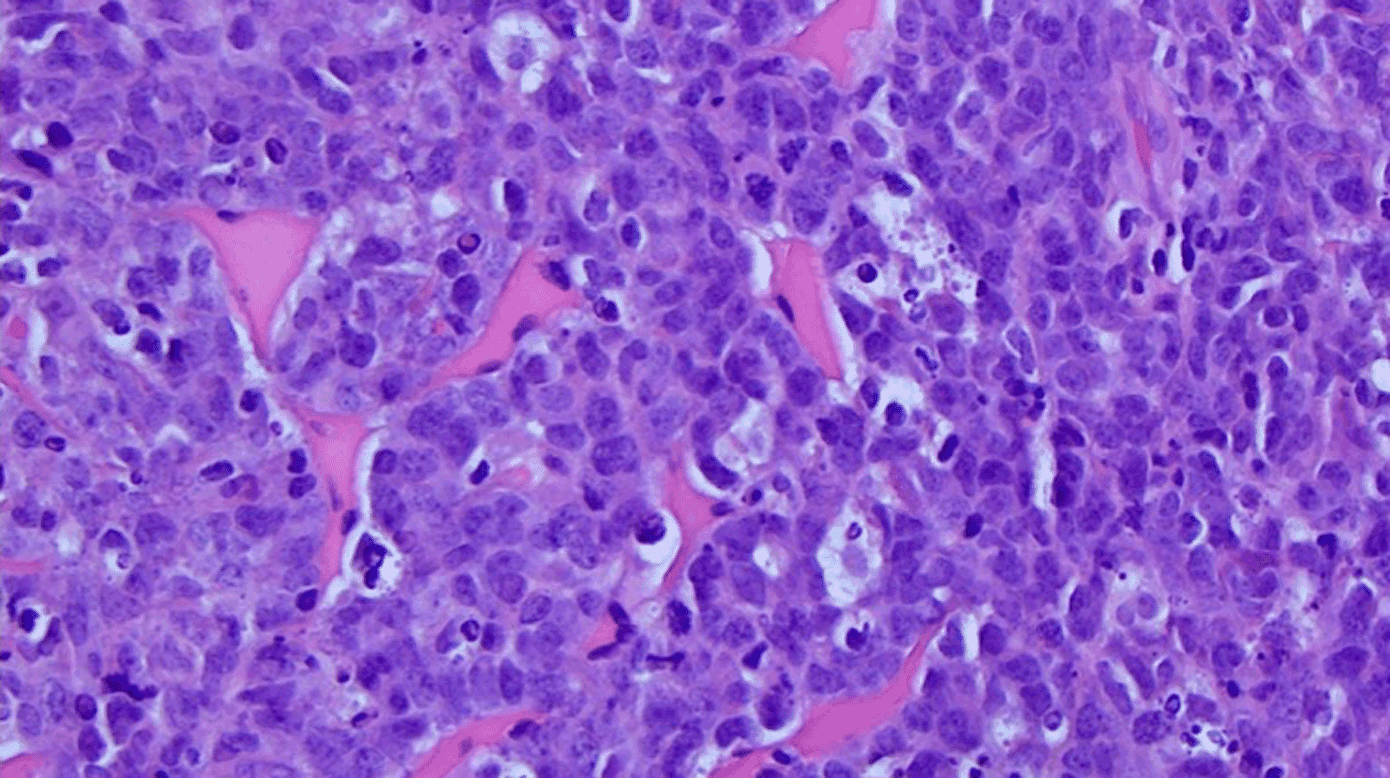

Perifert blodudstryg og flowcytometri, biopsi fra glandler samt PET-CT påviste leukæmiseret BL stadie IV med knoglemarvsinvolvering og ekstranodal affektion i mammae og ovarier (Figur 1 A). En MR-skanning viste let opladning langs højresidig n. facialis (Figur 1 B). Histologiske tests viste klassisk BL med Ki-67 på 100% og MYC-translokation (Figur 1 C).